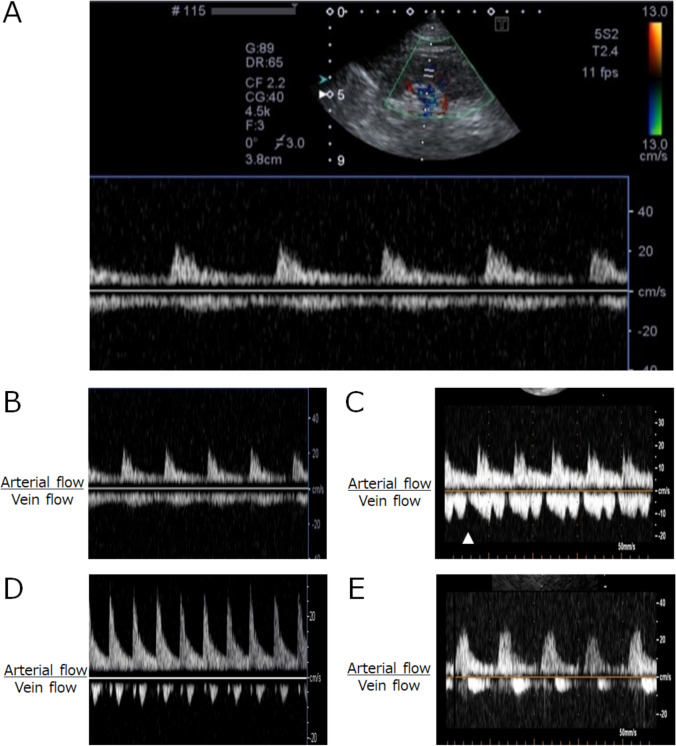

Objective: Intrarenal vein flow (IRVF) abnormalities can predict cardiovascular events including heart failure. This study aimed to evaluate the utility of short IRVF scans during routine comprehensive transthoracic echocardiography (TTE) examinations in a standard TTE laboratory.

Methods: We screened consecutive patients who underwent elective TTE at our Ultrasound Imaging Laboratory between March 2018 and July 2019 and prospectively enrolled those who completed a 5 min IRVF scan during the 30 min TTE procedure.

Results: Among the 2101 screened patients, 1326 were included in the study cohort (age: 73 ± 13 years, 756 men). IRVF abnormalities were detected in 13 (1.0%) patients. Twenty-one cardiac events were observed (1.6%, 21/1326): one myocardial infarction and 20 heart failures. Cumulative survival probability plots were generated using the Kaplan-Meier method within 6 months after the TTE index day and assessed using the log-rank test. The plots revealed significantly worse prognoses in patients with elevated right arterial pressure (RAP) and abnormal IRVF, when compared to normal RAP or normal IEVF (p < 0.0001 and p < 0.0001, respectively). In a receiver operating curve analysis to predict the occurrence of cardiovascular events, E/e' had moderate predictive potential (area under the curve: 0.795, p < 0.0001), and the combination of E/e' and IRVF abnormality had better predictive potential than did E/e' alone (p = 0.043).

Conclusion: Although rarely observed on TTE, IRVF abnormalities improve the ability of E/e' to detect cardiac events, especially heart failure. Further large-scale prospective studies are required to confirm our findings.